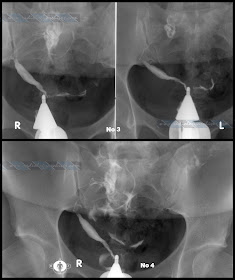

Case Courtesy: Πολύδωρος Π. Αμπατζής, MD Radiologist

Ιστορικό: Άτοκος γυναίκα 27 ετών με ελεύθερο ιστορικό σε έλεγχο γονιμότητας.

Ευρήματα: Έγινε δυο φορές σκιαγράφηση. Την πρώτη τοποθετήθηκε ο σαλπιγγογράφος για το αριστερό κέρας. Επανατοποθετήθηκε ο σαλπιγγογράφος με κοντότερο ρύγχος και απεικονίστηκε το δεξιό κέρας.

Διάγνωση: Δίκερως διτράχηλος μήτρα με κοινό έξω τραχηλικό στόμιο.

Ιστορικό: Άτοκος γυναίκα 27 ετών με ελεύθερο ιστορικό σε έλεγχο γονιμότητας.

Ευρήματα: Έγινε δυο φορές σκιαγράφηση. Την πρώτη τοποθετήθηκε ο σαλπιγγογράφος για το αριστερό κέρας. Επανατοποθετήθηκε ο σαλπιγγογράφος με κοντότερο ρύγχος και απεικονίστηκε το δεξιό κέρας.

Διάγνωση: Δίκερως διτράχηλος μήτρα με κοινό έξω τραχηλικό στόμιο.